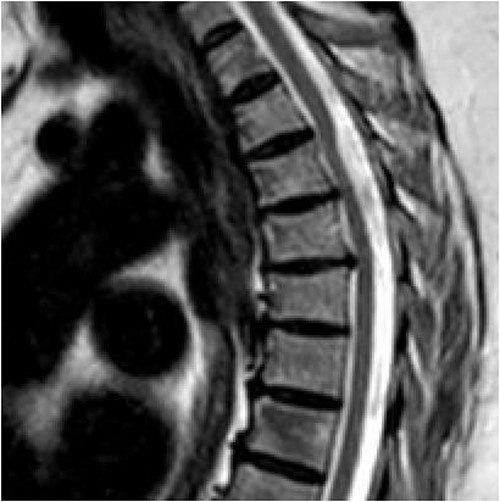

A 62-year-old woman presented with an extensive, multi-decade history of lower back pain that has progressively gotten worse over the last year. She initially presented in clinic with lumbar pain that radiated down her left anterior thigh, as well as significant thoracic pain that worsened with activities. She has a past surgical history of three lumbar laminectomies in 1983, 1988, and 1995 that caused temporary relief of her lumbar radiculopathy. In clinic, she stated that, during long periods of standing, she will experience buttock and lower extremity pain, as well as pain radiating to her anterior thigh and groin. She also said that she had increased difficulty with balance, causing her to use a rolling walker for ambulation. Physical examination demonstrated myelopathic symptoms with 3+ reflexes in both lower extremities and positive Babinski sign bilaterally. MR imaging of the spine was ordered and showed an arachnoid web displacing the spinal cord at the level of T3 (Fig. 3). Her current symptoms were treated nonoperatively with an epidural steroid injection that caused 80% relief of symptoms for 2–3 weeks. Three months later, she returned with increased bilateral shooting pain in the interscapular blade region. The patient will return in 6 months to proceed with a repeat thoracic MRI to evaluate for any interval changes.

Dorsal indentation demonstrated in thoracic spine preoperatively (Patient C).